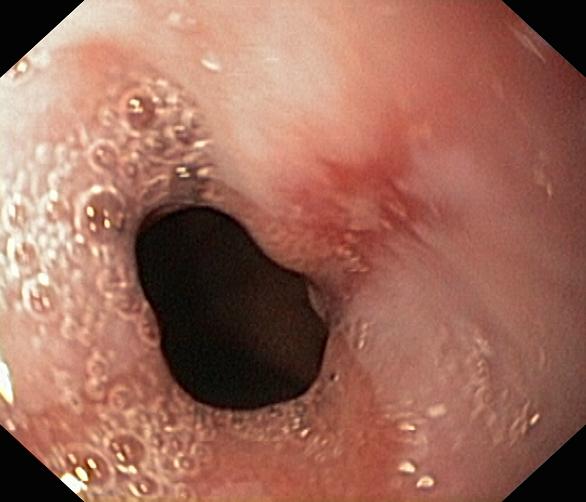

Choroba refluksowa